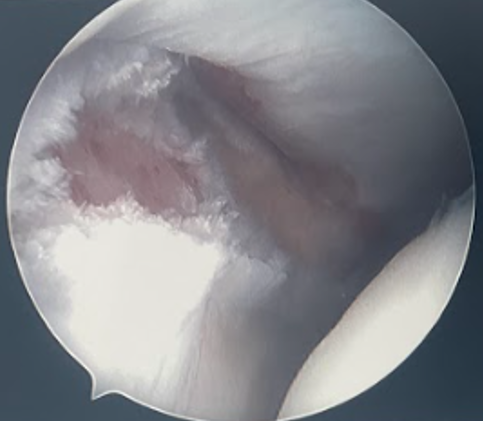

Arthroscopy

Inspect the syndesmosis with external rotation stress test

- widening > 2mm between tibia and fibula

- dynamic widening

- can also visualize AITFL and PITFL

Disruption of the syndesmosis and widening / diastasis with external rotation stress